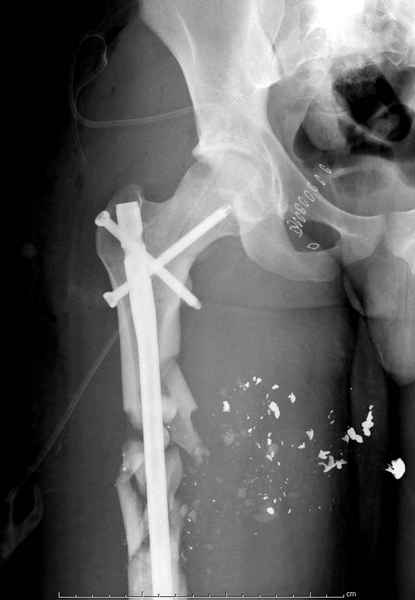

2 перелом бедра